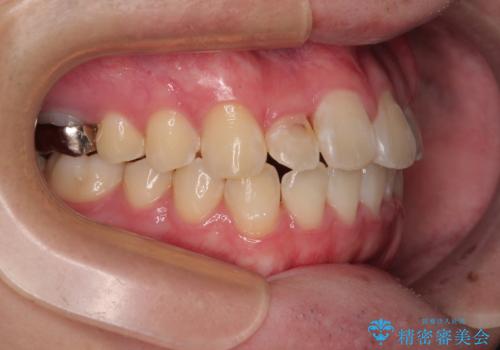

適切な診断と装置の選択により、1年という短期間でここまで改善できます。

見た目の美しさだけでなく、将来のむし歯や歯周病リスクを減らすことにもつながる治療です。